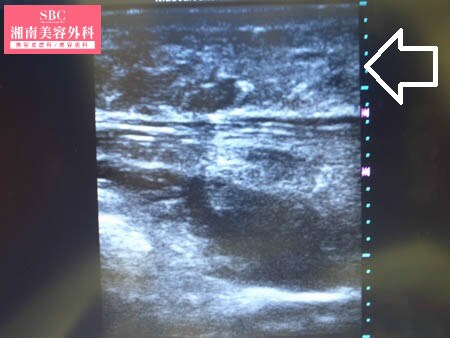

No.119503【脂肪吸引】日本人初!ライポマティック認定医であるあの有名な根こそぎ竹田先生の劇的ビフォーアフター!〜発表会でドレスを着るためにおなかの脂肪吸引をする!術中上腹部3Dタッチビュー〜